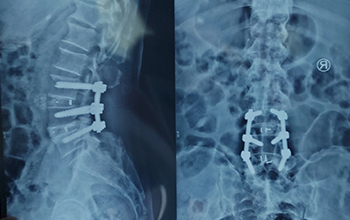

At CZMEDITECH, we are dedicated to providing reliable orthopedic solutions through real clinical success. Each surgical case reflects our continuous innovation in spinal fixation, trauma management, joint reconstruction, maxillofacial repair, and veterinary orthopedics. By integrating advanced manufacturing technology with the expertise of experienced surgeons, we ensure every implant delivers safety, precision, and long-term recovery.

Explore below a selection of clinical cases that demonstrate how our CE-certified implants help restore mobility, stability, and confidence in patients worldwide.